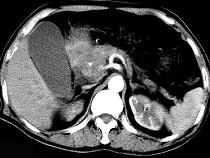

问题 男,50岁,黄疸进行性加重、腹部胀痛不适、食欲减退、体重减轻、上腹部可触及肿块,CT如图,最可能的诊断为()

选项 A.急性胰腺炎 B.慢性胰腺炎 C.胰头癌 D.腹膜后淋巴瘤 E.转移瘤

答案 C